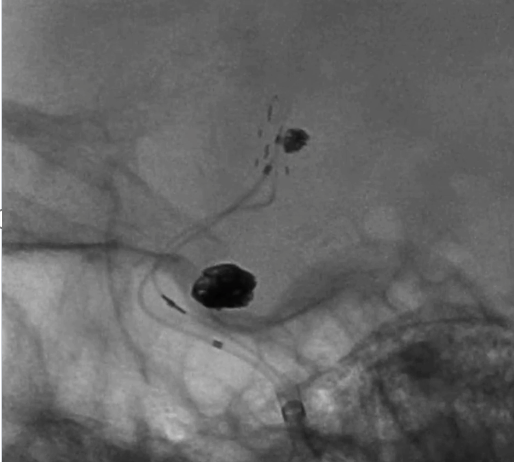

治疗结果

术后正侧位造影:Raymond Ⅲ级

术后支架重建:支架打开良好,近端Marker位于颈内动脉分叉处

术后Vaso CT未见出血,患者神清语利,神经系统查体阴性。